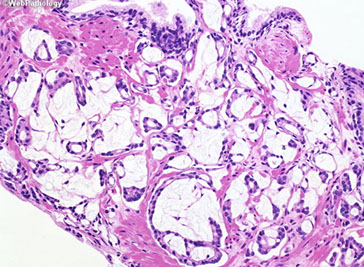

Clear Cell Cribriform Hyperplasia

Typically seen in the transition zone (vs HG-PIN in peripheral zone) has crowded cribriform glands c clear cytoplasm, sometimes growing as a nodule and in other instances more diffusely

- key distinguishing feature from HG-PIN is the lack of nuclear atypia, and at least some of the glands have a basal cell layer (not seen in HG-PIN)

- immunostaining for abs to basal cells not very helpful since both clear cell cribriform hyperplasia and HG-PIN have patchy basal cell layers

Occurs in transition zone, mostly in TURP for urinary obstructive sx and rarely needle bx

- some consider it a cribriform variant of BPH

- made of numerous cribriform glands separated from each other by modest amt of stroma in pattern of nodular hyperplasia

- if florid, can infiltrate stroma diffusely and have back-to-back glands

- if misdiagnosed, would be Gleason 4+4=8

Micro: epithelial cells have clear cytoplasm and small bland nuclei c inconspicuous or small nucleoli

- around man of the glands is a strikingly prominent basal cell layer c row of cuboidal darkly stained cells beneath the clear cells

- basal cells may form small knots at the periphery of some of the glands

- basal cells can occasionally have small nucleoli

- basal layer may also be inconspicuous or incomplete

- although usually unnecessary, HMWK stains basal cells

Distinguishing bwt clear cell cribriform hyperplasia and cribriform PIN can be difficult

- easier to diff from ca, which doesn't have basal cells

- clear cell cribriform hyperplasia probably unrelated to AC